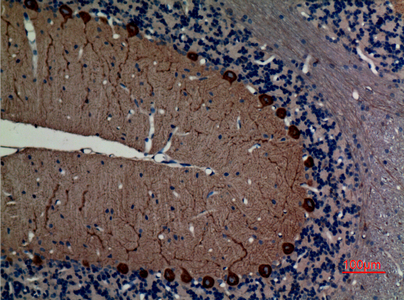

WB,IHC-P,IF-P,IF-F,ICC/IF,ELISA

WB 1:500-1:2000, IHC-P 1:100-300, ELISA 1:40000, IF-P/IF-F/ICC/IF 1:50-200